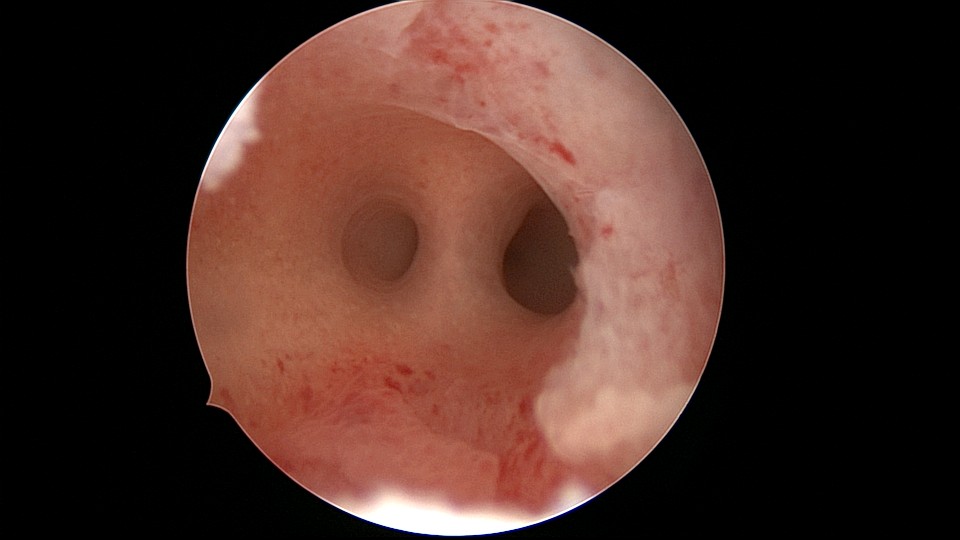

患者21岁,G2P0,两次胎停清宫,月经量减少,眉山某医院B超示宫腔容积小,2021年7月宫腔镜探查,见宫腔两侧、宫底部及左侧宫角粘连,单极电针分粘,恢复宫腔形态,显露双侧输卵管开口。2021年9月宫腔镜二探取球囊,宫腔形态正常,双侧输卵管开口可见。2022年9月自然妊娠12+周,我院建卡,2023年5月孕38+周剖宫产分娩。2025年3月宫腔镜取胚1次,现25岁,G4P1,剖宫产1次。